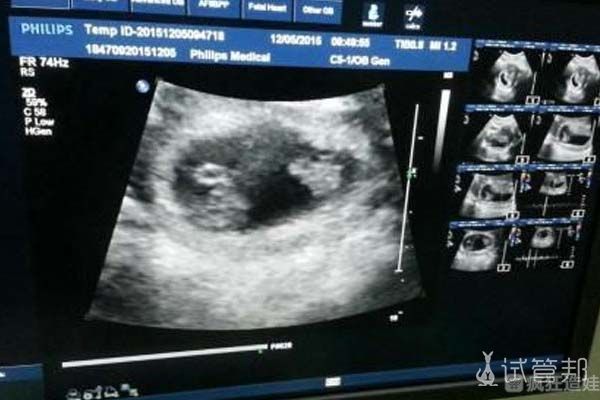

第二天到医院做了检查,等到第5天的时候,孕酮内膜均已达标,就可以开始进行移植了。在移植后第10天,我到医院进行了抽血验孕,一次成功,宝宝已将着床了。